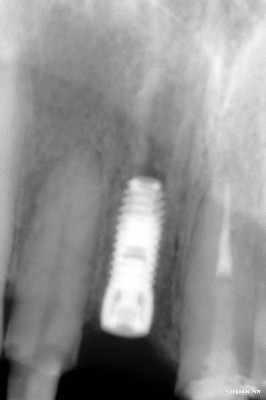

Implante colocado en incisivo central derecho

Secuencia de colocación de implante